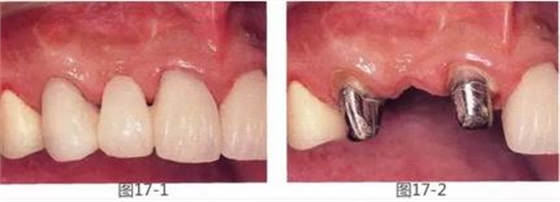

圖17-1,2 術(shù)前。右上2的橋體部唇側(cè)存在凹陷。

圖17-7 將羥磷灰石和結(jié)締組織填入封閉后。

圖17-8 愈合后10個月。